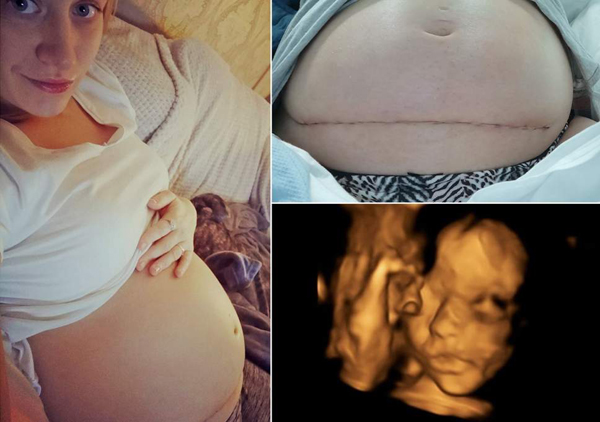

పూర్తి వివరాల్లోకి వెళ్తే… 26 ఏళ్ల ఒక మహిళ గర్బంతో ఉంది.గర్బంలో ఉన్న శిషువు ఆరోగ్యం గురించి తెలుసుకునేందుకు స్కానింగ్ నిర్వహించారు.స్కానింగ్లో గర్బస్థ శిశువుకు స్పినా బిఫిడా అనే అరుదైన జబ్బు ఉందని తేలింది.దాంతో శిశువు వెన్నెముక సరిగా పని చేయదు.దాంతో పుట్టిన తర్వాత ఆ శిశువు ఇబ్బంది పడుతుందనే ఉద్దేశ్యంతో ఆ తల్లిదండ్రులు ఇద్దరు కూడా గర్భస్రావం చేయించాలని నిర్ణయించుకున్నారు.వారు 20 వారాల తర్వాత గర్బస్రావంకు ప్రయత్నిస్తున్నట్లుగా తెలియడంతో ఒక ప్రముఖ హాస్పిటల్ వారి సమస్యకు పరిష్కారం చూపుతామంటూ ప్రకటించింది.

గర్బంలో ఉన్న శిశువుకు ఉన్న సమస్యను తాము తొలగిస్తామని, శిశువు బయటకు వచ్చిన తర్వాత పూర్తి ఆరోగ్యంగా ఉండేలా తాము చేస్తామంటూ హామీ ఇచ్చారు.హాస్పిటల్ వైధ్యులు హామీ ఇవ్వడంతో ఆ జంట గర్బస్రావంకు వెళ్లలేదు.వైధ్యులు ఆపరేషన్ చేసి 20 వారాల పిండను బయటకు తీసి, ఆ పిండంకు ఒక ఆపరేషన్ చేయడం వల్ల ఆ శిశువు సమస్యను తొలగించడం జరిగింది.ఆ శిశువుకు ఆపరేషన్ ముగిసిన తర్వాత మళ్లీ తల్లి గర్బంలోనే ఆ శిశువును ప్రవేశ పెట్టడం జరిగింది.

ఆ శిశువు తల్లి గర్బం నుండి బయటకు వచ్చి మళ్లీ లోనికి వెళ్లిన అరుదైన శిషువుగా గుర్తింపు దక్కించుకోబోతుంది.ప్రస్తుతం ఆ మహిళ మరియు మహిళ గర్బంలో ఉన్న శిశువు ఇద్దరు కూడా ఆరోగ్యంగా ఉన్నట్లుగా వైధ్యులు చెబుతున్నారు.ఇది వైధ్య శాస్త్రంలో అద్బుతంగా చెబుతున్నారు.పిండానికి ఏదైనా సమస్య ఉంటే అబార్షన్కు వెళ్లకుండా ఇది మంచి పద్దతి అంటూ వైధ్యులు చెబుతున్నారు.